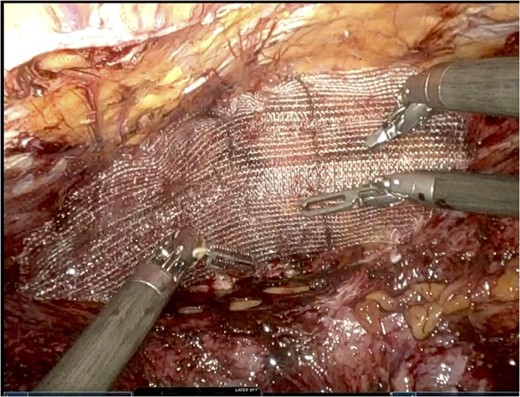

He was admitted for nasogastric decompression and underwent an upper endoscopy with benign findings. Once stable, he was discharged and optimized as an outpatient by adhering to a high-protein liquid diet. He underwent a scheduled robotic-assisted transabdominal preperitoneal (r-TAPP) repair of a type 4 anterior diaphragmatic hernia with mesh. The robot was docked and targeted with four 8 mm robotic ports across the mid-abdomen. A moderately sized hernia containing a loop of the transverse colon was identified. This was gently reduced (Fig. 3).

The falciform ligament was taken down with bipolar cautery. A peritoneal flap was created commencing about 4 cm inferior to the defect. A preperitoneal dissection was then performed to create the flap and to reduce the sac out of the mediastinum (Fig. 4).